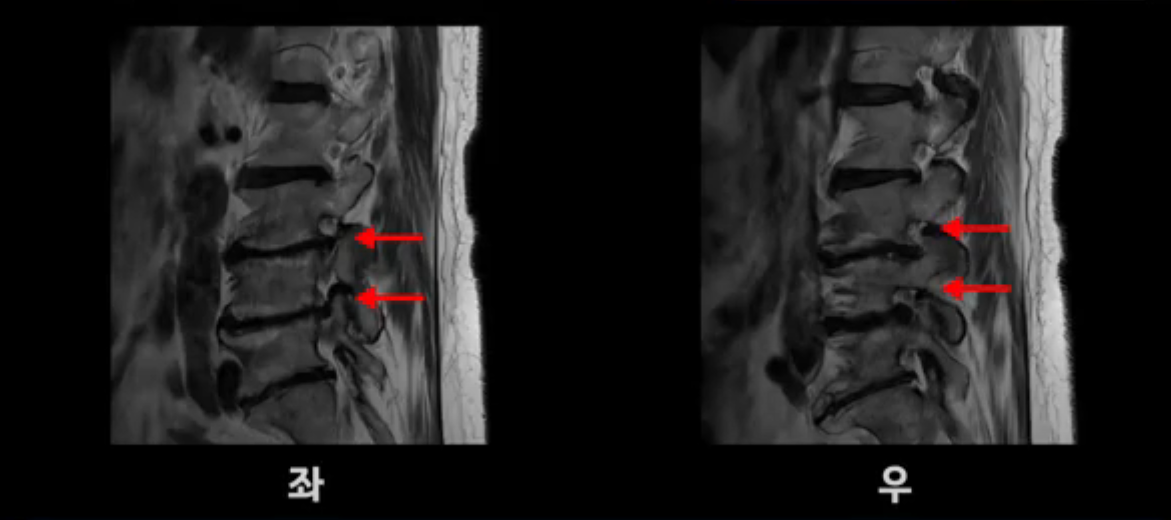

보시다시피 이 환자분은 허리 여러 마디가 다 안 좋습니다. 4마디 디스크 높이가 심하게 주저 앉았습니다.

신경이 빠져나가는 추간공들이 좌우 다 좁아져 있고

척추관도 좁아져 있습니다.

이렇게 신경 구멍들이 좁아져 있어서 신경눌림 증상이 엉덩이와 다리에 생기는데, 이런 증상들은 근육과 매우 밀접한 관련이 있습니다.

협착증 환자분들 중 걸을 때만 다리가 저리고 아픈 분들이 있고, 반면에 앉거나 누울 때도 허리, 엉덩이, 다리가 아프고 저린 분들이 있습니다. 이 환자분처럼 앉아도 누워도 아픈 분들일수록 근육 문제가 심한 분들이고, 이런 분들은 걸을 때만 아픈 분들에 비해 수술 결과도 더 안 좋고 따라서 수술 이후에도 아플 가능성이 높습니다. 꼭 알아두시길 바랍니다. 저희 모커리한방병원에서는 걸을 때만 다리가 저리고 아픈 분들을 단순형 협착증, 걸을 때 말고도 앉거나 누울 때도 허리, 엉덩이와 다리가 저리고 아픈 분들을 복합형 협착증이라고 부르는데, 이 환자분이 바로 복합형 협착증 환자분입니다.